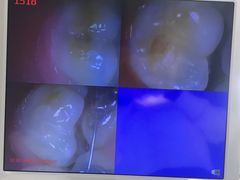

• 优伢仕口腔(汽车西站店)

• -优伢仕口腔(汽车西站店)

善勇优美的小滨 | 23-08-29

星球_3615 | 23-08-21

hwy1998 | 23-08-09